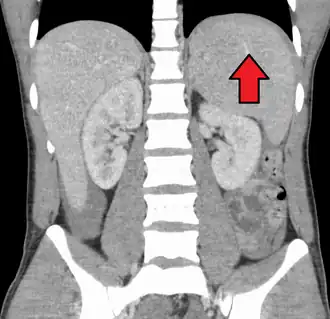

Spleen enlargement is common in the second and third weeks, although this may not be apparent on physical examination. Rarely, the spleen may rupture.[27] There may also be some enlargement of the liver.[25] Jaundice occurs only occasionally.[16][28]

Splenomegaly is a common symptom of infectious mononucleosis, and healthcare providers may consider using abdominal ultrasonography to get insight into the enlargement of a person's spleen.[61] However, because spleen size varies greatly, ultrasonography is not a valid technique for assessing spleen enlargement. It should not be used in typical circumstances or to make routine decisions about fitness for playing sports.[61]